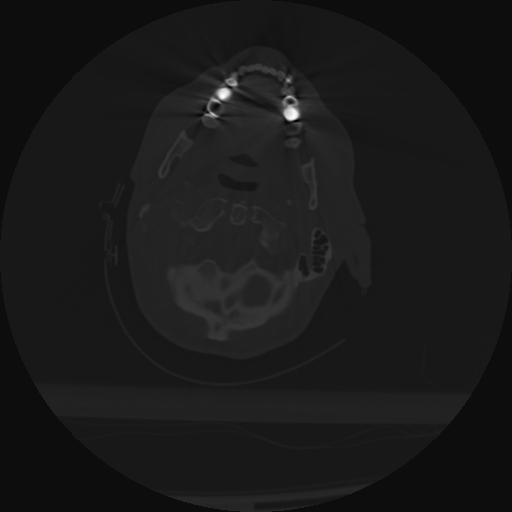

22 ANGIO,CE,Vol,0.5,ANGIO,,